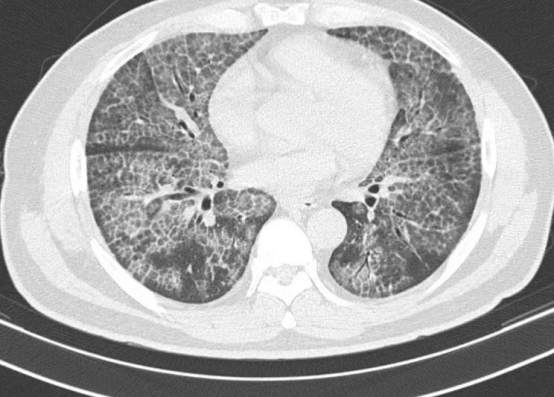

我院副院长、呼吸与危重症科主任医师薛青耐心问诊并完善肺部CT 检查后,初步判断其为极为罕见的肺泡蛋白沉积症,他安抚患者,可为肺部 “洗个澡”,缓解病症。后续经气管镜肺活检等检查,林先生最终确诊该病。

方桂桔表示,肺泡蛋白沉积症是以肺泡腔及细支气管内沉积大量非脂溶性磷脂蛋白样物质为主要特征的一种极其罕见肺部疾病,发病率仅为3.7/100万。主要可表现为咳嗽、呼吸困难及咳痰,也可表现为咯血、乏力、胸痛等不典型症状。目前全肺灌洗仍是主要的治疗方法,即在全身麻醉状态下行双腔支气管插管,一侧肺通气,一侧肺灌洗,反复予 37℃生理盐水灌洗,采用物理手段清除肺泡表面活性物质,以缓解临床症状。在此,特别提醒:如出现长时间不明原因咳嗽、活动后气喘等症状,应及时就医,避免延误诊治。